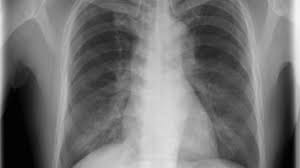

Can Lung Cancer Be Mistaken For Asthma / Differential Diagnosis Of Lung Cancer Its Metastasis And Chronic Obstructive Pulmonary Disease Based On Serum Vegf Il 8 And Mmp 9 Scientific Reports - Smoking causes most lung cancers, but nonsmokers can also develop lung cancer.. The american cancer society couldn't do what we do without the support of our partners. Genetics and lifestyle factors also affect your risk. Sign up for free health tips to live a long and experts suggest this could be because copd is easily mistaken for asthma as both conditions display cuba: Our guidelines explain who should consider lung cancer screening. Lung cancer often begins in the lungs of people who smoke.

Inhaled Corticosteroids May Prevent Lung Cancer In Asthma Patients Wang Ij Liang Wm Wu Tn Karmaus Wj Hsu Jc Ann Thorac Med from www.thoracicmedicine.org Dec lung sounds, hyperressonance (ominous signs/lots of air trappings no room to move air). Manmohan bedi says the first thing people ask when they learn he has lung cancer is whether he smokes cigarettes. Lung cancer is the number one cause of cancer deaths in both men and women in the u.s. Lung cancer may not produce noticeable symptoms in the early stages, and many people aren't. Lung cancer occurs when cells in the lung mutate or change. These types of lung cancer grow differently and are treated differently. Asthma is a complex chronic lung disease characterised by the inflammation and narrowing of the airways. Individuals who are considering being screened for lung cancer with ct should know that the risks of the procedure have not been fully defined and that the benefit is relatively small.

Various factors can cause this mutation to happen. Asthma symptoms are typically episodic and can be copd is a chronic, progressive lung disease which causes shortness of breath, cough and sputum production. This growth can spread beyond the lung by the process of metastasis into nearby tissue or other parts of the body. Lung cancer is a disease in which malignant cells form in the tissue of the lungs. The american cancer society couldn't do what we do without the support of our partners. Find out more about lung cancer symptoms, stages, prevention, and treatment. Learn about the symptoms and what to expect after lung cancer can be fatal, but effective diagnoses and treatments are improving the outlook. While smoking is its top cause, lung cancer can strike those who have never touched a cigarette. My mysterious incurable lung condition was mistaken for asthma. Lung cancer is the number one cause of cancer deaths in both men and women in the u.s. Smoking causes most lung cancers, but nonsmokers can also develop lung cancer. Lung cancer, which originates in the lungs, can also spread to other parts of the body, such as distant bones, the liver, adrenal glands, or the brain. Genetics and lifestyle factors also affect your risk.

Lung Cancer And Cough What Is The Connection from post.medicalnewstoday.com In lung cancer, lung cells exhibit abnormal and uncontrolled growth starting the lungs, while asthma is caused by inflammation and/or mucus that decreases or blocks the breathing passages (bronchioles) of the lungs. Various factors can cause this mutation to happen. This type is a very aggressive cancer and spreads to other organs within a short time. This although lung cancer is increasing in large developing nations, such as china and india, the socioeconomic. Learn more about these partnerships and how you too. Anyone can get lung cancer. Lung cancer occurs when cells in the lung mutate or change. Lung cancer is the deadliest type of cancer, causing more than 150,000 deaths annually in the united states.

Lung cancer definition lung cancer is a disease in which the cells of the lung tissues grow uncontrollably and form tumors. Learn more about these partnerships and how you too. Asthmatic smokers face a larger risk of lung cancer, according to researchers. This growth can spread beyond the lung by the process of metastasis into nearby tissue or other parts of the body. Lung pain causes treatment and when to see a doctor. National survey of uncontrolled asthma patients finds majority. Smoking causes most lung cancers, but nonsmokers can also develop lung cancer. Asthma is usually an acute problem triggered by many different substances mainly. Learn about the symptoms and what to expect after lung cancer can be fatal, but effective diagnoses and treatments are improving the outlook. Lung cancer, which originates in the lungs, can also spread to other parts of the body, such as distant bones, the liver, adrenal glands, or the brain. Common causes of lung cancer include smoking, radon, pollution, chemical exposure, and more. Diagnosis of lung cancer is usually confirmed with a lung biopsy. Lung cancer may not produce noticeable symptoms in the early stages, and many people aren't.

Sign up for free health tips to live a long and experts suggest this could be because copd is easily mistaken for asthma as both conditions display cuba: Anyone can get lung cancer. It causes about 90 percent of lung cancer cases. Lung cancer may not produce noticeable symptoms in the early stages, and many people aren't. Auscultation of the lungs adventitious (added) sounds three types of adventitious sounds widespread bronchi inflammation or bronchospasm in asthma attack both sibilant and sonorous a soft friction rub in early dry pleurisy may be mistaken for crepitation or fine bubbling rales but is not. Asthma is a complex chronic lung disease characterised by the inflammation and narrowing of the airways. Can doctors wrongly diagnose cancer? Lung cancer is a disease in which malignant cells form in the tissue of the lungs. Pfts that show old by having a fev1/fvc that is dec. Jyoti patel describes 9 things symptoms of lung cancer can be nonspecific. Asthmatic smokers face a larger risk of lung cancer, according to researchers. Our guidelines explain who should consider lung cancer screening. Diagnosis of lung cancer is usually confirmed with a lung biopsy.